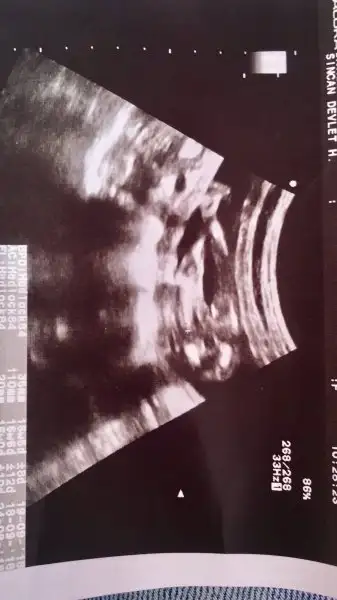

Canim geçenlerde duymuştum bebeğin kafasının arkasında kist mi ne varmış kadına sonlandırılması lazım demişler ama haftası ilerledikçe kaybolmuşArkadaşlar doktordan çıktık yer ayağımdan kaydı sanki rüya olsun lütfen bu yaşadıklarım. Bebek 10+5 olmuştu kalbi atıyordu ama bebeğin kafasının arkasında 3 mm sıvı var dedi kafa tasını sarmış.Nedeni tam belli değil çünkü bebek çok küçük dedi.Böyle bir durunla karşılaşan böyle birşey duyan var mı? Bir hafta sonra tekrar gel başka doktorlara da yönlendirecekmiş beni gerekirse gebeliği sonlandıracak.Şoka girdim inanamıyorum. Allahım sen yardım et

Tebrik ederim canim super :)Kızlar kötü haber paylaştım iyi haberi de paylaşayım. Ayrıntılı ultrasonda bir problem görmedi doktor ense kalınlığı içinde evet sorundur ama 3.5 mm ve sonrası sorundur dedi. Şimdi geriye nifty test sonucu kaldı. Veeee cinsiyeti de kız